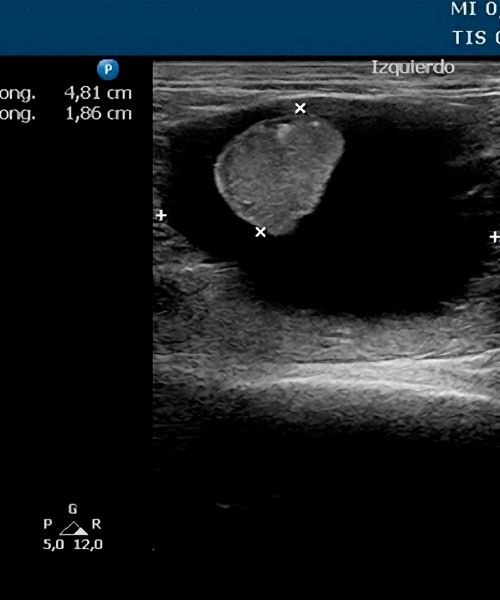

Valido la precisión diagnóstica comparando las imágenes ecográficas con los hallazgos quirúrgicos reales.

Garantizo transparencia y confianza exhibiendo en este apartado casos reales con su correlación intraoperatoria documentada.